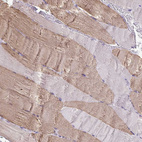

Immunohistochemistry analysis in human heart muscle and pancreas tissues using HPA019763 antibody. Corresponding MYL2 RNA-seq data are presented for the same tissues.